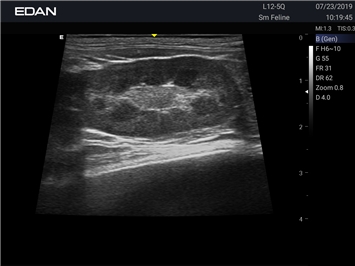

Ветеринарный ультразвук одним нажатием. Система Acclarix AX2 VET разработана с целью обеспечить бескомпромиссную производительность по доступной цене. Наличие уникальных двойных аккумуляторов в легком корпусе массой 4,5 кг из магниевого сплава позволяет системе Acclarix AX2 VET удовлетворять все потребности ветеринарных исследований, сохранив низкую стоимость.

EDAN Acclarix AX2 VET представляет собой специализированную ветеринарную ультразвуковую систему, сочетающую высокую производительность с доступной ценой. Благодаря продуманной конструкции и передовым технологиям, система обеспечивает качественную диагностику животных различных видов.

B-режим, Двухмерное сканирование:

Да